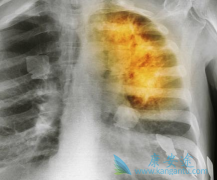

• 肺癌晚期还有救吗?如何治疗肺癌晚期

肺癌晚期还有救吗?如何治疗肺癌晚期

一般来说肺癌患者只要被确诊为晚期,患者和家属就会很迫切的想知道,治疗情况如何?晚期有救吗?虽然说癌症目前还不能达到完全治愈的目的,但仍有不少晚期肺癌患者带瘤生存,治疗效果不错,生活质量也很高的案例。肿瘤不止手术切除、放化疗、中医治疗等 ...

• 肺癌晚期可以治好吗是患者非常关注的问题

肺癌晚期可以治好吗是患者非常关注的问题

患者得了肺癌,能活多久是大家关心的问题,很多人都希望肺癌能够治好,但是大部分人觉得肺癌晚期基本上治疗无望,只能等待死亡。很多患者在肺癌晚期时来咨询康安途海外医疗,本身在医生的建议下打算治疗的,寻求二次建议。那么 肺癌晚期可以治好吗 ?   ...

• 肺癌晚期能治吗?靶向治疗肺癌疗效如何

肺癌晚期能治吗?靶向治疗肺癌疗效如何

早期肺癌比较好治疗,手术经常是第一方案,患者五年生存率可达80%-90%。通常到了肺癌晚期,手术治疗的难度非常大,综合患者的体质、病情状况也无法接受手术治疗,而且 肺癌晚期 易发生转移或者扩散的情况。   所以,止痛、控制病情、更好的活着、活得 ...

• 肺癌晚期能治吗?治疗肺癌主要方法有哪些

肺癌晚期能治吗?治疗肺癌主要方法有哪些

总所周知肺癌是非常难以治愈的,特别是到了肺癌晚期的时候。病人的身体状态都不是特别好,治疗的难度也非常大。那么, 肺癌晚期能治吗 ?要怎么治疗呢?接下来。大家就跟小编一起来看看吧。   肺癌晚期怎么治疗:化学治疗,这些年来,肺癌的化疗很受关 ...